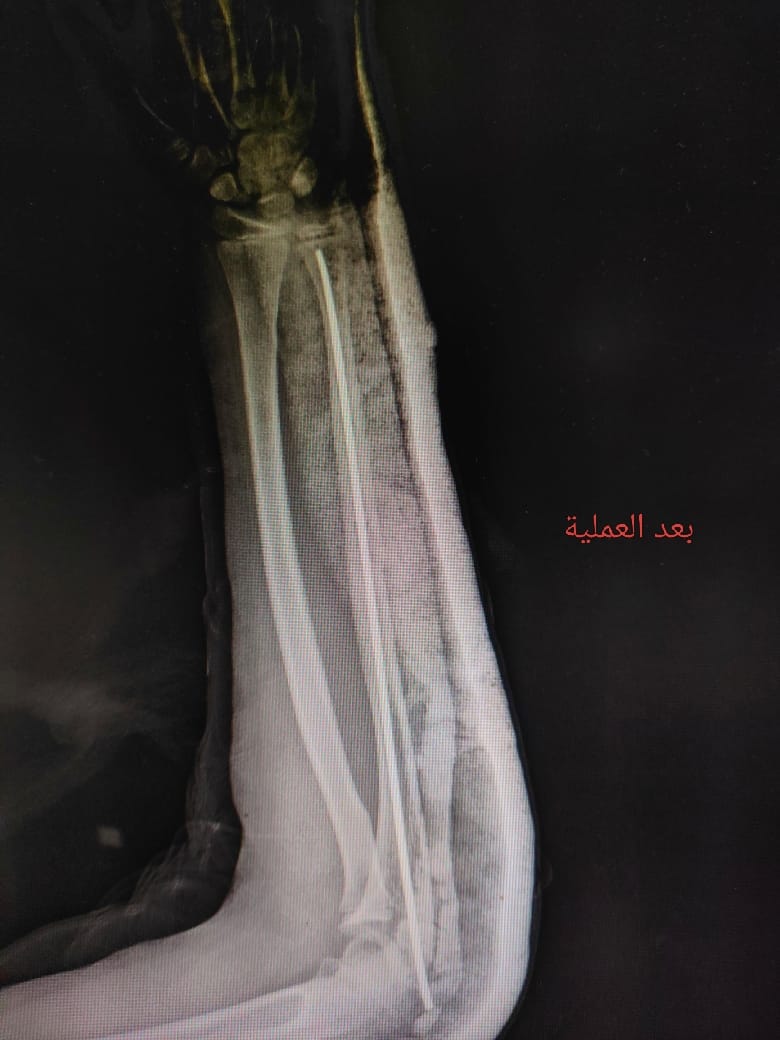

استقبلت مستشفى طلخا المركزي بمحافظة الدقهلية طفلة تعاني من كسر في عظمة الزند الأيسر، حيث جرى التعامل الفوري مع الحالة ونقلها إلى غرفة العمليات لإجراء التدخل الجراحي اللازم.

وذلك تنفيذًا لتعليمات الدكتور خالد عبد الغفار نائب رئيس الوزراء ووزير الصحة واللواء طارق مرزوق محافظ الدقهلية وبرعاية الدكتور حمودة الجزار، وكيل وزارة الصحة بالدقهلية، وإشراف مباشر من الدكتور السيد فاروق، وكيل المديرية للطب العلاجي،، والدكتورة لاميس حمدى، مدير مستشفى طلخا المركزي، حيث تم إجراء العملية بنجاح وتركيب مسمار نخاعي مرن بالزند الأيسر.